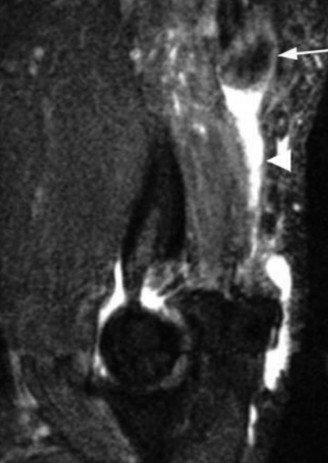

After evaluating the MRI, the patient is diagnosed with a complete rupture of the pectoralis major tendon (Fig. 2–79). What is the recommended first step in management?

Figure 2–79

The correct answer is (C). Although pectoralis major muscle (PMM) injuries are

primarily diagnosed clinically, MRI is the imaging modality of choice to evaluate a PMM tendon injury. The extent and location of the injury can many times be assessed with MRI. The Tietjen’s classification system can be used for PMM injuries. Type I is a contusion or sprain. Type II is a partial tear. Type III injuries are complete tears and further classified by anatomic location: III-A (muscle origin), III-B (muscle belly), III-C (musculotendinous junction), III-D (tendinous insertion). Further subclassification were suggested including III-E (bony avulsion from the insertion) and II-F (muscle tendon substance rupture). Type II and Type III injuries have been reported at rates of 9% and 91%, respectively. Among complete tears, type III-D has been reported as the most common (65%). Ultrasound is a reasonable alternative to MRI, particularly if its use means avoiding delay of surgical repair. Ultrasound is much more user-dependent. CT will not allow adequate soft tissue evaluation. Further radiographic evaluation is incorrect because a radiograph of the injured shoulder has already been obtained. The radiographic findings are often normal, but the clinician should look for bony avulsions. The characteristic findings on radiographs are soft tissue swelling and absence of the PMM shadow.